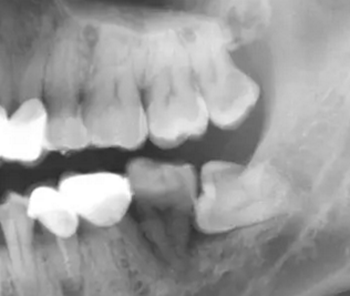

2.牙根折斷。牙根折斷是拔牙術中常出現(xiàn)的并發(fā)癥,造成牙根折斷的原因很多。如:所拔牙的牙冠破壞廣泛,或有較大充填體,對于一些老年人的牙,死髓牙,根管治療后的牙,牙體組織的脆性大,容易折斷,牙根外形變異,出現(xiàn)彎曲,根端肥大,粗大多根,額外根,根分叉過大等情況,根周骨質因各種病理生理因素(慢性根尖炎,老年人等)致密性,造成彈性降低或牙根固連等都容易造成牙根折斷(對于短小的小于5mm的短根,根周無炎癥,取出創(chuàng)傷大者,可不拔除,后期觀察)。

a.上頜竇底位置低或根尖病變破壞了竇底骨質易發(fā)生斷根移入上頜竇。

9.口腔上頜竇交通??谇簧项M竇交通多發(fā)生于上頜磨牙取根致牙根移入上頜竇,竇底穿孔,也可因磨牙根尖病變致竇底骨質缺如,搔刮病變時穿破竇底,如小的穿孔(直徑2mm左右)可按拔牙后常規(guī)處理,使牙槽窩內形成以高質量的血凝塊,使其自然愈合。?

c.慢性感染。主要是由局部因素所致,如牙槽窩內遺留殘根、肉芽組織、牙石、碎牙片或碎骨片等異物。臨床表現(xiàn)為拔牙創(chuàng)經久不愈,留下一個小創(chuàng)口,創(chuàng)口周圍牙齦組織紅腫,可見少量膿液排出或有肉芽組織增生,一般無明顯疼痛。

防治:牙拔除術后應仔細清理牙槽窩,特別是慢性根尖周炎的患牙,根尖炎性病灶不刮治干凈,即可發(fā)生拔牙術后出血,也可形成慢性炎癥而長期不愈。多根牙拔除時應防止殘根遺留。如發(fā)生慢性感染,應拍攝X線片,了解牙槽窩內病變情況,是否有異物遺留,牙槽窩的愈合情況等,然后在局麻下,重新進行牙槽窩的刮治,讓血液充滿后,消毒紗布棉卷壓迫止血,并給予口服抗生素治療。